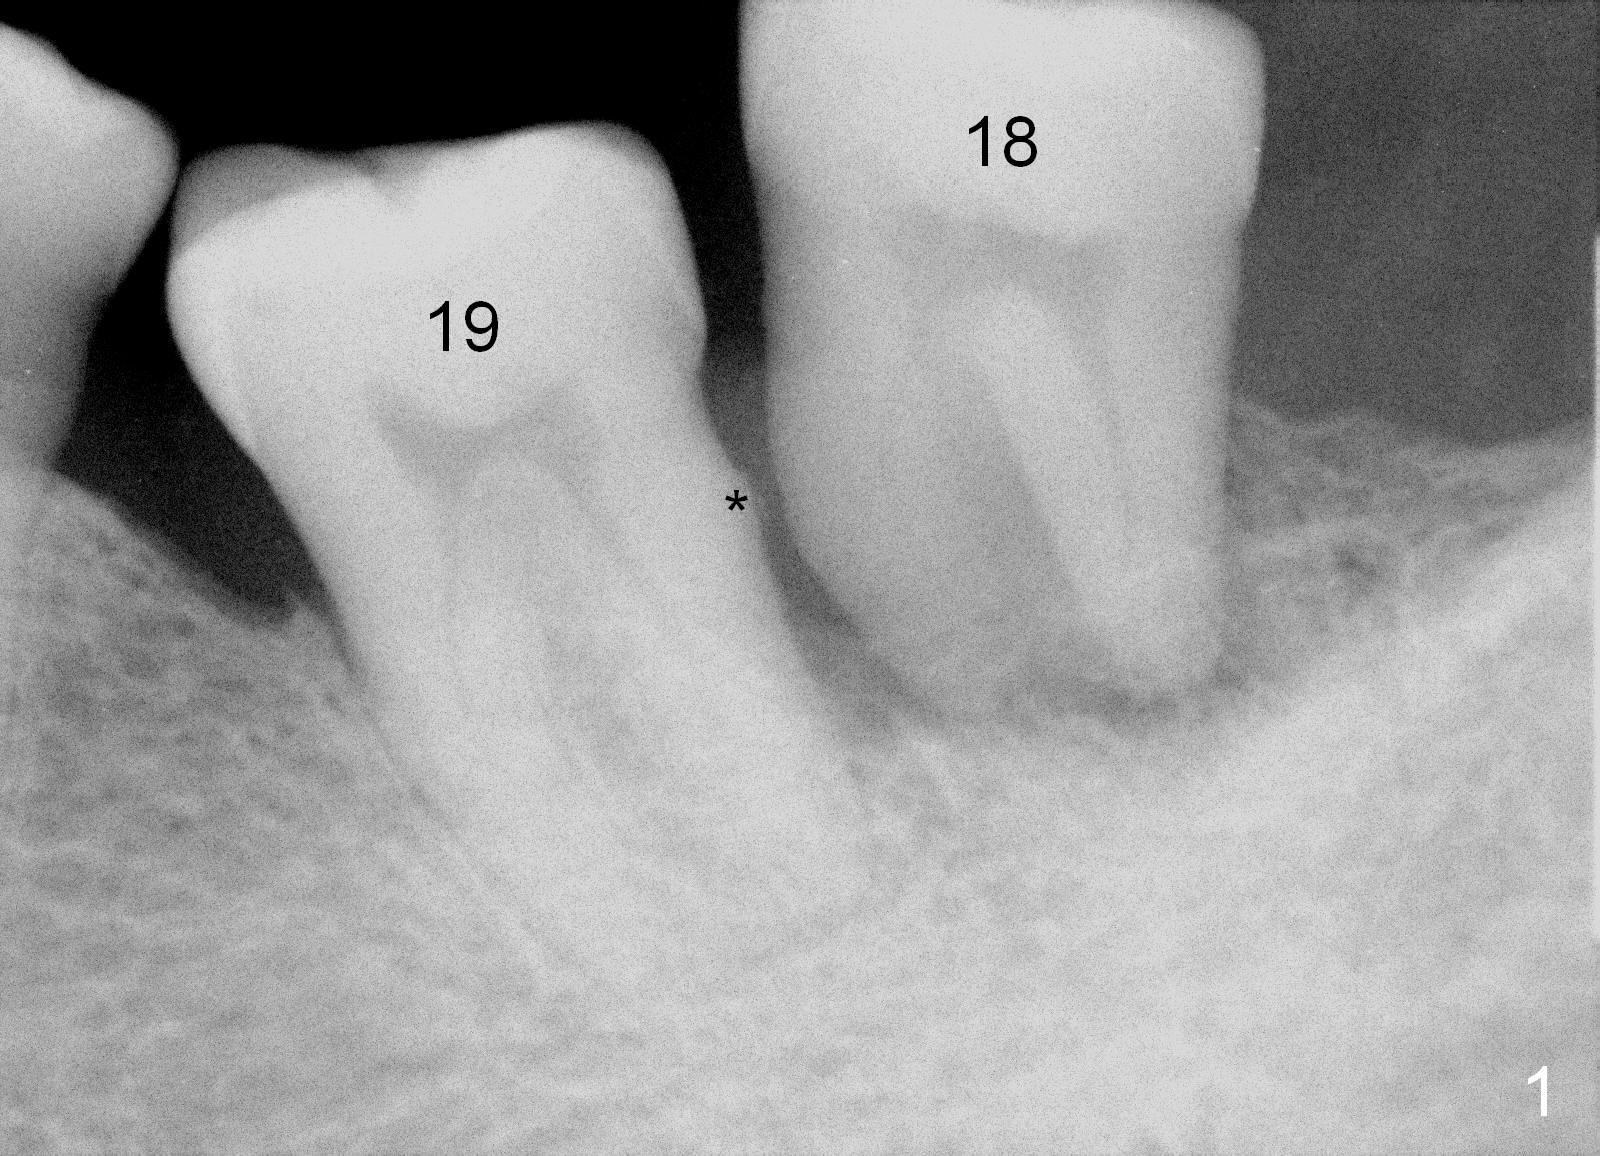

A 63-year-old man has periodontitis. The tooth #18 (probably 17) has mobility III (Fig.1). Three more PAs are taken with deeper placement of #2 sensor (Fig.2,6,7) to show the upper border of the Inferior Alveolar Canal (yellow dashed lines). The affected tooth has severe bone loss, especially mesially (Fig.2,3 (arrowheads)). No matter whether bone (Fig.4) or gingiva (Fig.5)-level implant is placed, the threads should be covered circumferentially by bone, native or grafted (red circles). In Fig.5, the threads are apical to black arrowheads, whereas the rough surface, which should be also contacted by bone, is the lower half above the black arrowheads.

Measures of infection control include pre- and post-op oral antibiotic and Chlorhexidine mouth rinse. Intra-op measures consist of sterile surgical field, intra- and extra-oral sterilization, removal of granulation tissue, application of antibiotic to the socket and copious irrigation. The distal root surface of #19 may have calculus and plaque (Fig.1 *). Scaling & root planing is to be done, followed by application of Emdogain and placement of bone graft.